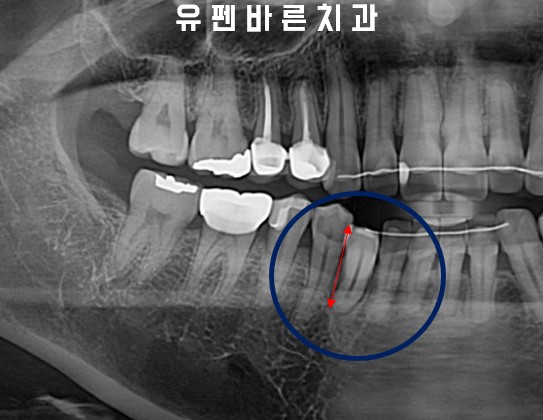

Adding buccal root torque on LR3

전,후 엑스레이 사진을 비교해 보시면

치아의 뿌리가 바로 서면서

교정 전, 후의 치아길이가

확연히 달라진 모습을

확인해 보실 수 있습니다!

엄청 앞으로 누워있던 치아를

인비절라인 교정을 통해

뿌리의 각도를 움직여

본래 치아의 모습으로

돌아왔습니다.